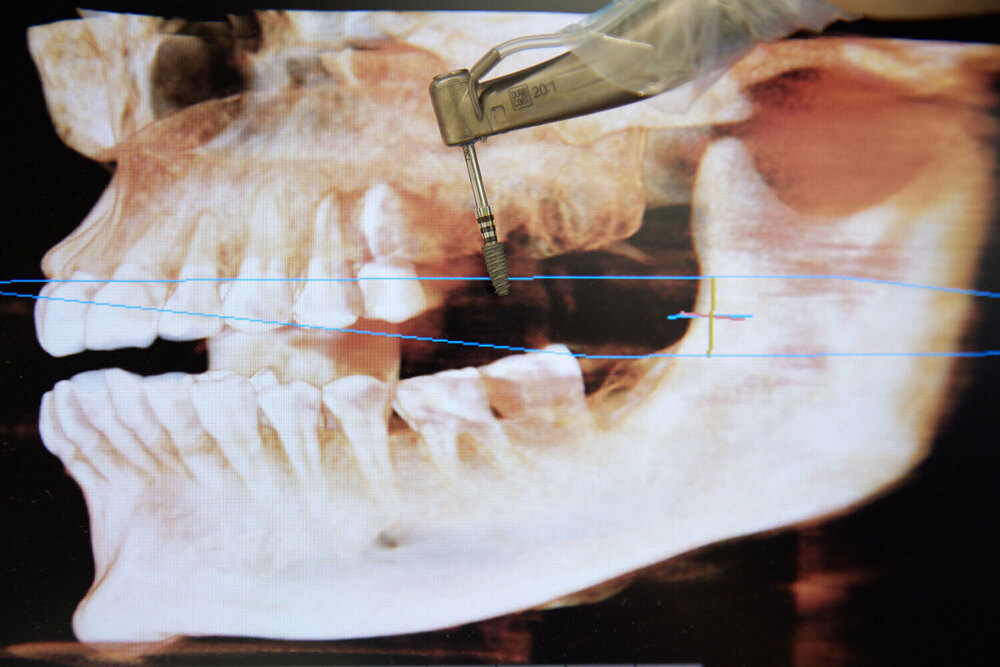

Un implant dentaire est une racine artificielle en titane, insérée dans l’os de la mâchoire pour remplacer une dent absente